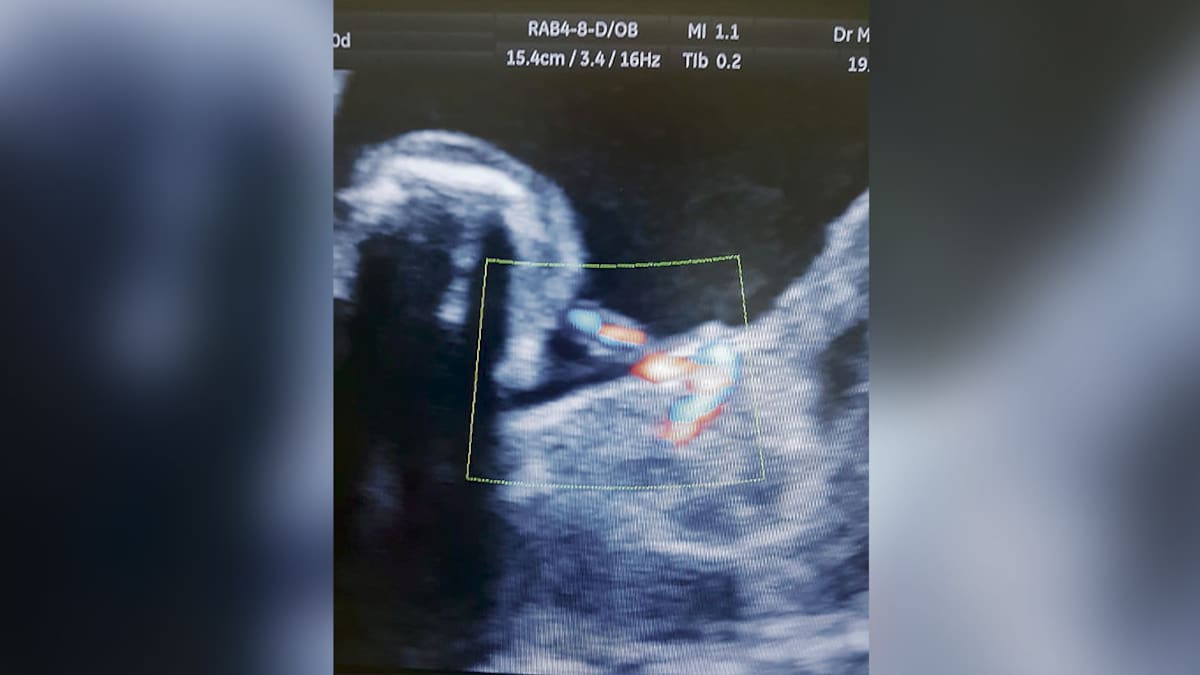

El ginecólogo informó que la madre llegó a la unidad de la Clínica La Merced con una ecografía de la semana 25, en la cual se reportaba que la bebé tenía un quiste. 'Nos dimos cuenta de que no era un quiste, sino un ‘fetico’ que estaba dentro del abdomen de su hermana que se llama Izamara', dijo.

Pasadas 24 horas le hicieron una cesárea a la bebé recién nacida, y le extrajeron del abdomen a su ‘hermanito’, que medía 45 milímetros y pesaba 14 gramos. 'El feto tenía brazos y piernas, sin embargo no tenía corazón, ni cerebro y murió al cortar el cordón umbilical que lo unía a su hermana', explicó Parra.